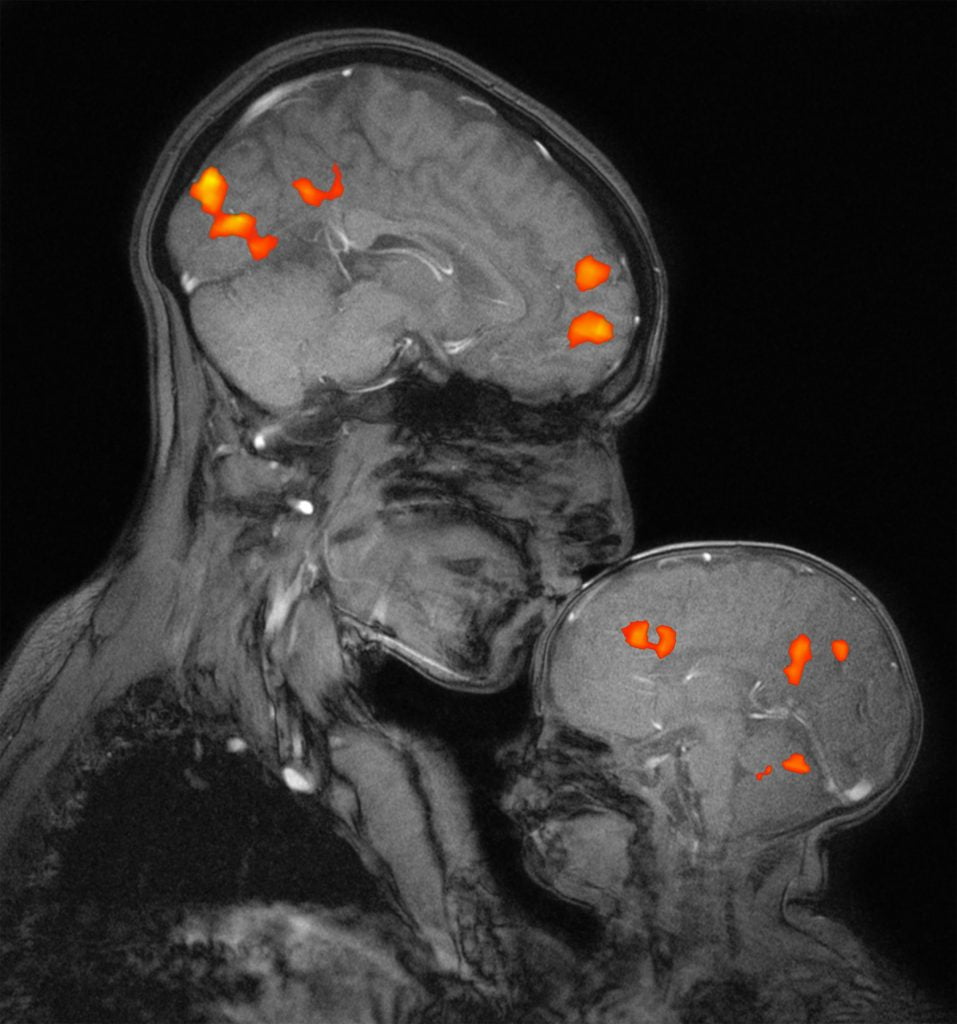

Le atipie precoci del neurosviluppo nello spettro autistico